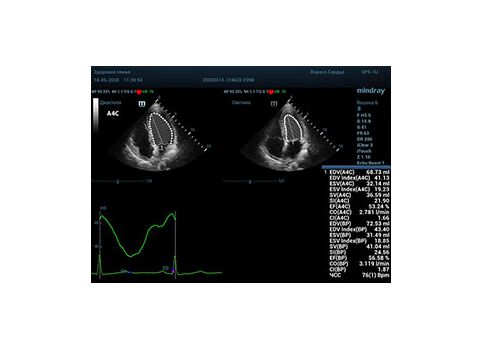

Что могут предложить современные приборы? Приборы нашего времени являются мощными вычислительными машинами, способными обрабатывать полученную информацию даже без помощи человека. Система автоматического вычисления фракции выброса – AUTO EF на приборах серии Resona компании Mindray сделает все за вас. За пару секунд прибор сам отыщет нужную фазу сердечного цикла и произведёт измерение и расчеты, а также покажет график изменения объема в сердечном цикле. От Вас требуется только получить качественное 4С и 2С сечение. Впрочем, прибор всегда оставляет возможность коррекции, если доктор имеет свое мнение на расположение точек планиметрии или момента измерения по ЭКГ каналу.